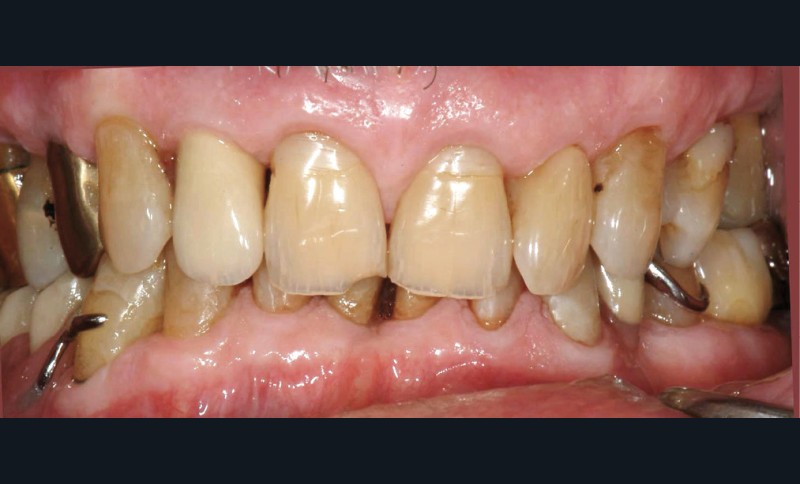

La prothèse partielle à armature métallique mandibulaire (PPAM) et la restauration du secteur antérieur à l’aide de matériau composite ont été réalisées en 2007. Le patient présente une occlusion de type classe II d’Angle génératrice de sévères abrasions du secteur incisif mandibulaire. Sur les photographies initiales (fig. 1a, b), on constate les prémices de traumas occlusaux (fracture de l’angle de 11, érosions des collets restaurés précédemment).